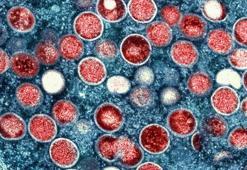

Avrupa'da aşı turizmi eleştirisiMaymun çiçeğine karşı aşı uygulamasına başlayan Avrupa ülkelerine İtalya da katılırken, koordinasyondan uzak ve dağınık aşı kampanyaları şikayetlere neden oluyor.

9.08.2022Dünya

ABD maymun çiçeği salgınını bir halk sağlığı acil durumu ilan ettiABD yönetimi, vakalardaki ani artışın ardından maymun çiçeği salgınını halk sağlığı acil durumu ilan etti. Karar, virüsün yayılmasını engellemek için aşıların, tedavilerin ve federal kaynakların dağıtımını hızlandıracak.

5.08.2022Dünya

Maymun çiçeğinden Avrupa'daki ilk ölüm İspanya'da gerçekleştiGüney Amerika ülkesi Brezilya'nın ardından ölümler Avrupa'ya sıçradı, İspanya'da hastalığa yakalananların sayısı 3 bin 750.

30.07.2022Dünya

Bakan Koca: Bir hastamızda maymun çiçeği hastalığı tespit edildiSağlık Bakanı Fahrettin Koca, bir hastada maymun çiçeği hastalığı tespit edildiğini duyurdu.

30.06.2022Gündem

Maymun çiçeğinde salgın ve mutasyon beklenmiyor! Kritik 3 yıl detayıİngiltere'de başlayıp Kuzey Amerika ve Avrupa ülkelerinde hızla yayılan maymun çiçeği virüsü akıllara, "İkinci bir pandemi kapıda mı?" sorusunu getirdi. Özellikle cinsel temas yoluyla bulaşmasıyla dikkatleri üzerine çeken ve AIDS'e yol açan HIV virüsünü hatırlatan hastalıkla ilgili uzmanlar çok çarpıcı açıklamalarda bulundu.

25.05.2022Gündem